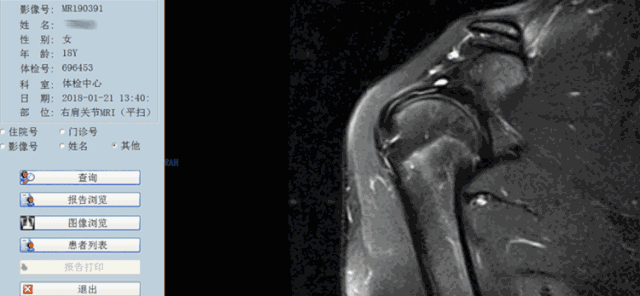

1期:肩袖尤其是冈上肌的水肿和出血,在年龄小于25岁的有症状患者中最为典型;

Neer分期提示我们,年龄是肩袖损伤诊断的重要因素,MRI诊断时也要注意这点,而且1、2期代表退变,应该选择保守治疗,3期为撕裂,也就是真正的肩袖损伤,大部分需要手术治疗。